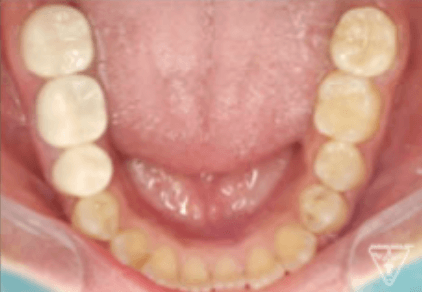

治療前

治療後